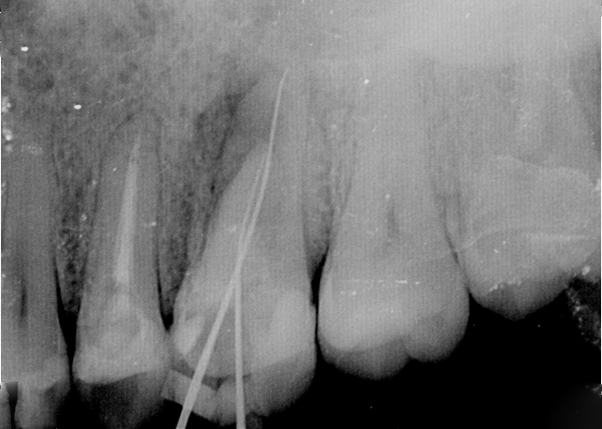

Endodonti (Kanal tedavileri,fiber post uygulamaları)